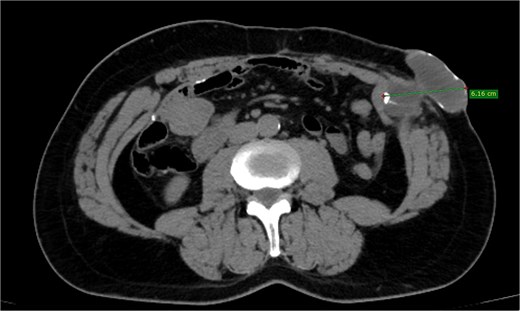

A 52-year-old Caucasian male presented with a palpable mass in the abdominal wall at the site of a previous colostomy. His surgical history included a colostomy performed at 15 months of age due to ileus, followed by restoration of digestive continuity 1 month later, as well as a cholecystectomy in adulthood. The patient was a smoker with no other known comorbidities. Physical examination revealed a firm, well-defined, non-tender mass in the area of the previous stoma. The overlying skin was intact, without signs of inflammation. Laboratory investigations, including tumor markers, were within normal limits. Contrast-enhanced computed tomography (CT) demonstrated a well-encapsulated cystic lesion located above the posterior sheath of the rectus abdominis muscle, without communication with the gastrointestinal tract. No lymphadenopathy or other suspicious findings were observed (Figs 1 and 2).

Depicting a well-encapsulated cystic lesion situated above the posterior sheath of the rectus abdominis muscle, with no communication with the bowel, measuring 6.16 cm.